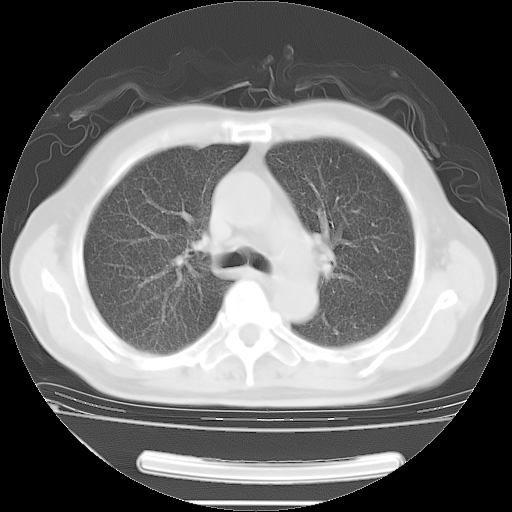

今天复查肺部CT,发现双肺广泛磨玻璃样改变。所以我把3月19日和5月9日相隔50天的肺部CT上传。请大家会诊。

5月9日肺部CT(在4月27日齐鲁医院肺部CT描述部分肺组织磨玻璃样改变,12天后肺组织广泛磨玻璃样改变)

2009年5月9日肺部CT

大致读了系列胸部CT:纵隔窗无明显异常,肺窗:从4、27至今:主要是双肺中下野外带可见毛玻璃样改变,目前处于急性肺泡炎阶段,至于原因考虑1、结替组织或胶原血管性疾病所致?2、恶性疾病如恶组在肺部所致的表现或细支气管肺泡癌?3、药物或其它原因如肺蛋白沉着症所致肺泡炎目前不太可能?总之,明天就去请我院的呼吸科、感染科、血液科和临免专家会诊哈。